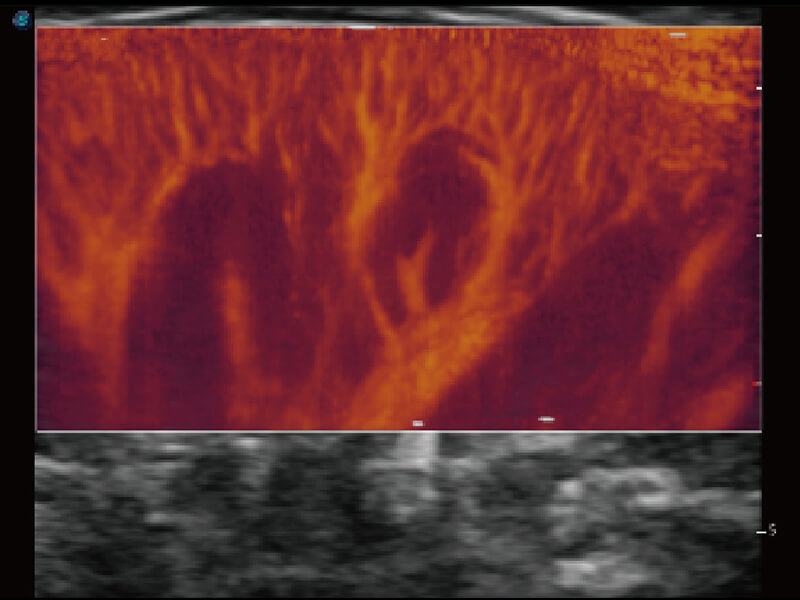

成像功能

性能优异的硬件架构,极大提升超声系统的运行效率和数据处理能力。相比以往超声成像系统,Wis+平台为您带来极快的响应速度和成像帧频,提升检查流畅度。

S60探头工艺,从前端信号处理每一个环节采集无损声学数据,真实还原组织原貌,再现解剖细节。